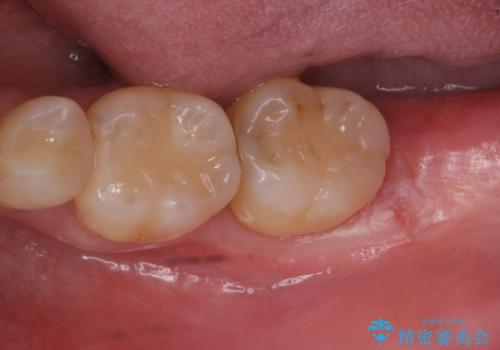

e-maxインレーによる治療

- 定期検診で来院してレントゲンを撮ったところ

歯と歯の間にう蝕ができていました。

拡大鏡下でう蝕を全て除去してe-maxインレーにて治療を行いました。